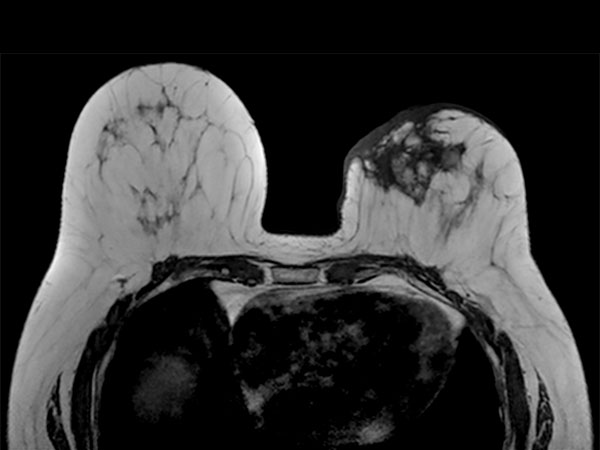

Axial T1w TSE